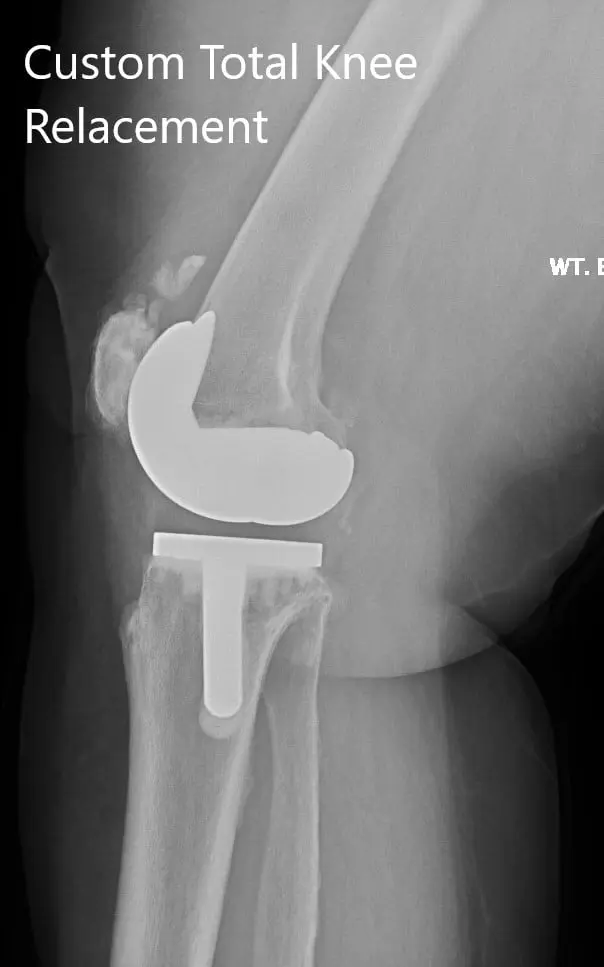

Postoperative X-ray showing the lateral views of both knees.

IMPLANTS USED: Customized knee replacement systems left and right. Bilateral polyethylene size 8 mm and patella size 32 mm x 6 mm.